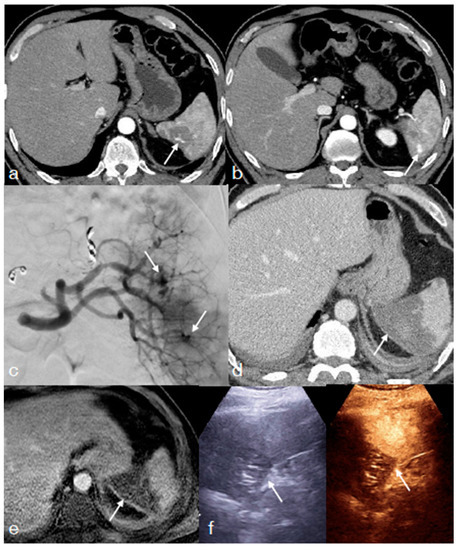

- Di Serafino, M.; Iacobellis, F.; Schillirò, M.L.; Ronza, R.; Verde, F.; Grimaldi, D.; Dell’Aversano Orabona, G.; Caruso, M.; Sabatino, V.; Rinaldo, C.; et al. The Technique and Advantages of Contrast-Enhanced Ultrasound in the Diagnosis and Follow-Up of Traumatic Abdomen Solid Organ Injuries. Diagnostics 2022, 12, 435. [Google Scholar] [CrossRef] [PubMed]

- Miele, V.; Piccolo, C.L.; Sessa, B.; Trinci, M.; Galluzzo, M. Comparison between MRI and CEUS in the follow-up of patients with blunt abdominal trauma managed conservatively. Radiol. Med. 2015, 121, 27–37. [Google Scholar] [CrossRef] [PubMed]